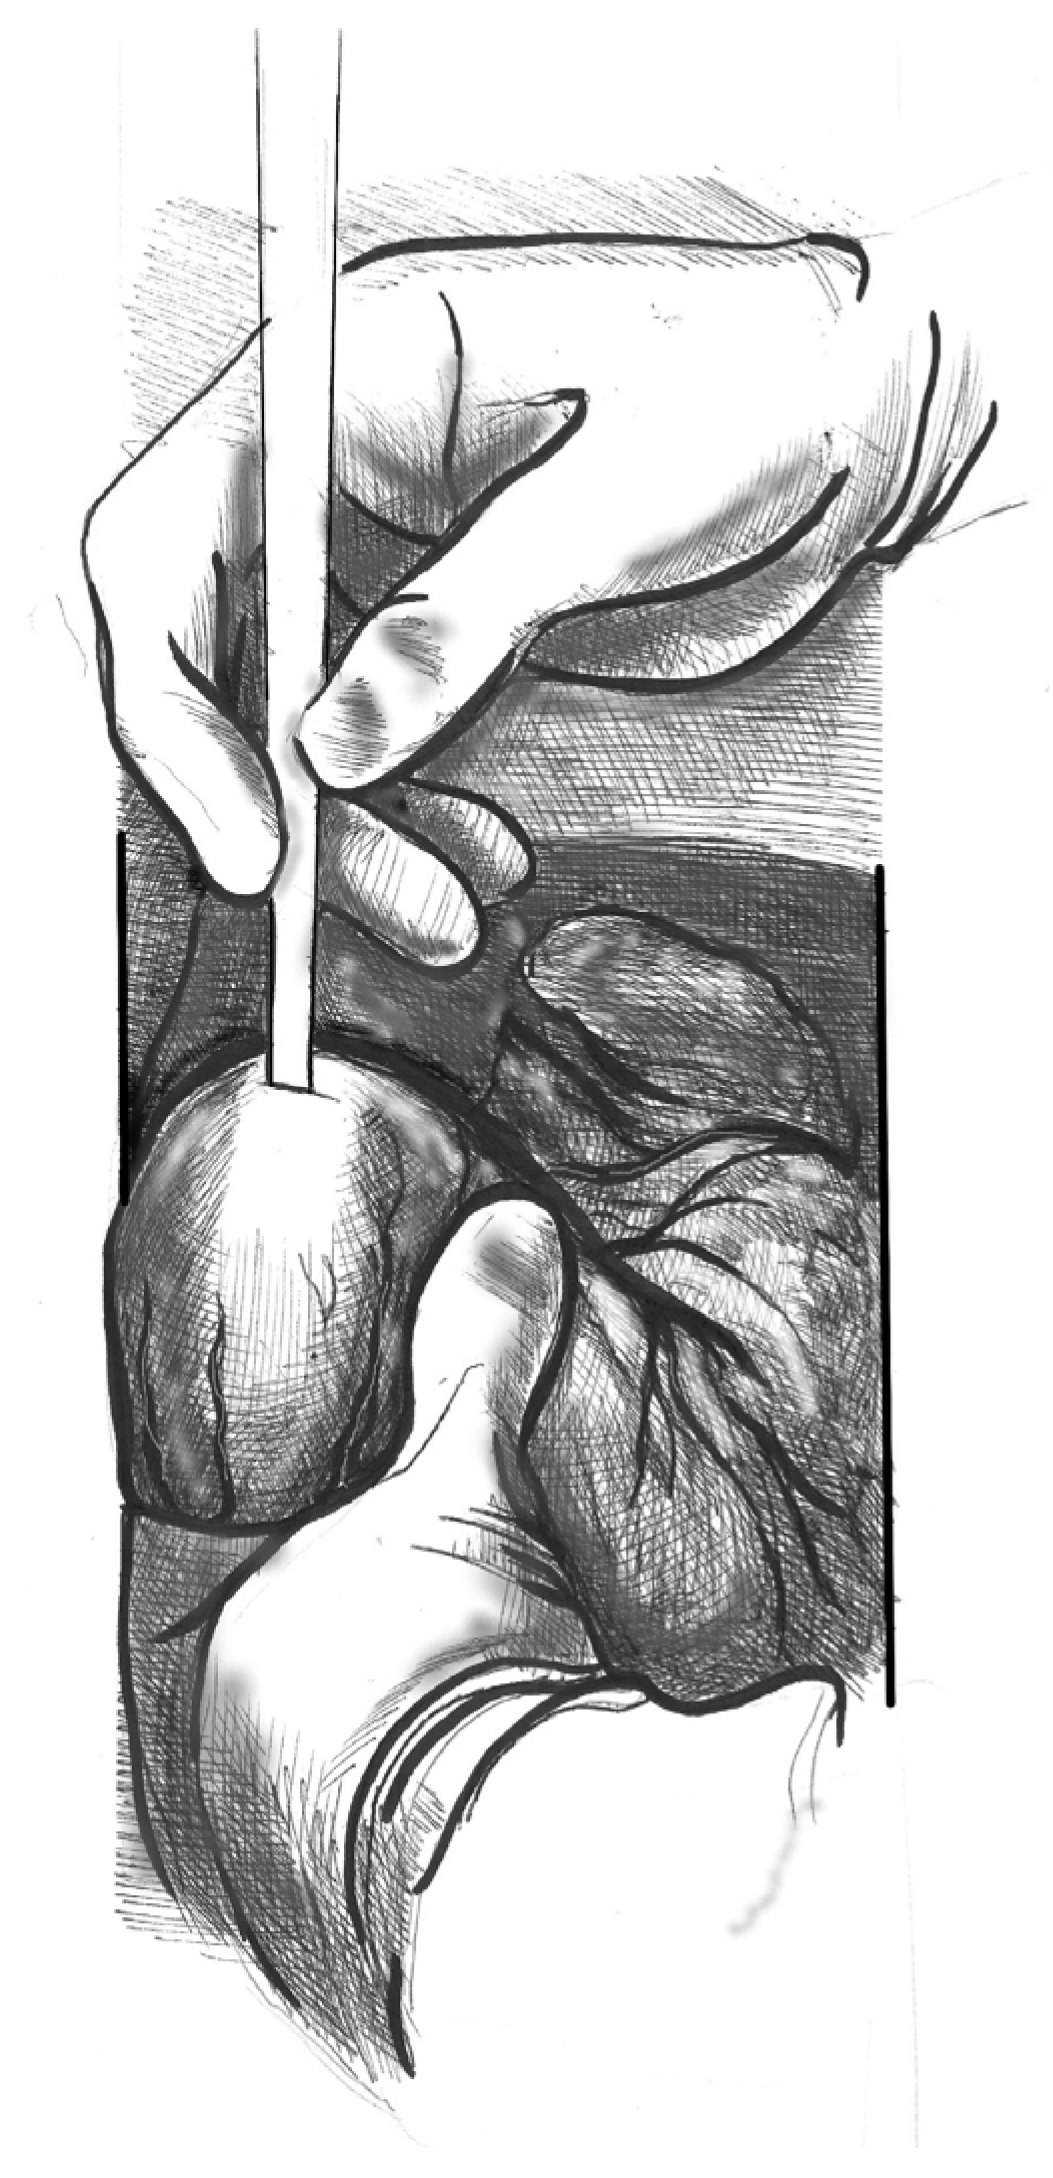

- Figure 2. Make a small (approximately 1 cm) apical incision with a No. 11 blade. The incision should be oriented cranially towards the aortic valve. Insert the cannula through the apex.